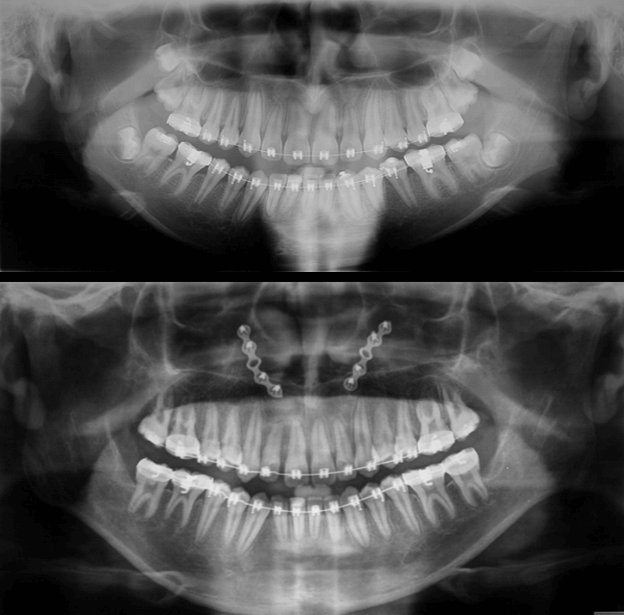

Radiografía Panorámica Comparativa

Radiografía Panorámica Final

Radiografía Panorámica Inicial

Se puede evidenciar la elongación del cóndilo mandibular izquierdo